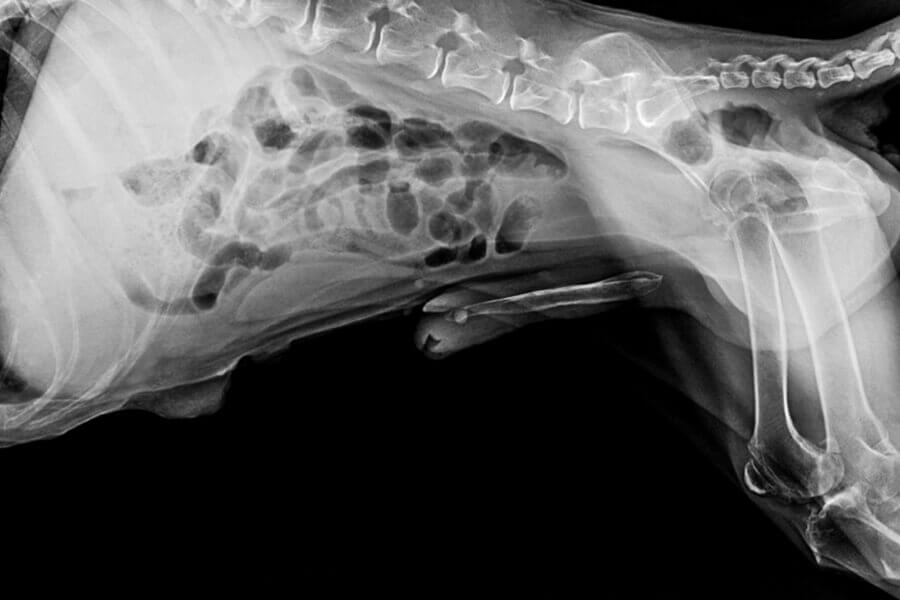

レッグペルテス病とは「大腿骨頭壊死症」とも呼ばれ、太ももの骨の先端にある大腿骨頭(骨盤と連結している骨)への血流が阻害されて起こる病気です。

何らかの原因で大腿骨頭への血流が阻害されてしまうと骨は徐々に壊死していき、犬は次第に歩くことが困難になってしまいます。

レッグペルテス病が進行すると、壊死した部分は頻繁に骨折するようになり、強い痛みをともないます。

ただし、レッグペルテス病は保存療法によって完治する病気ではなく、最終的には大腿骨頭の切除や人工関節形成手術を受ける必要があります。

一度壊死してしまった大腿骨頭は、時間が経っても元に戻ることはありません。